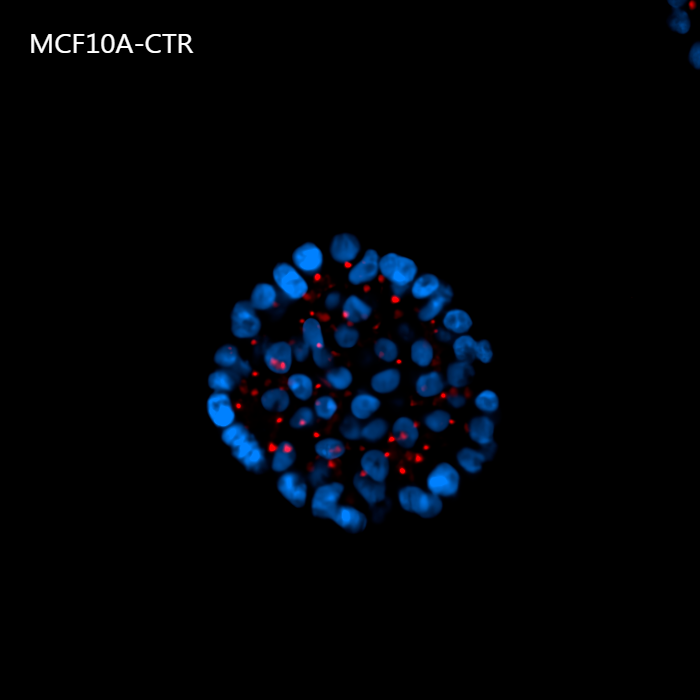

Figure 4 shows a maximum intensity projection (MIP) of 60 um Z-stack of non-malignant (A) and tumorigenic (B) acini. By providing homogeneous illumination over the entire 25 mm field of view (FOV), the X-Light V3 confocal spinning disk allowed us to analyze a large number of acini, reducing the number of images required to obtain robust data and, therefore, minimizing acquisition time.

A

Figure 4: MIP from 60 um Z-stack of non-malignant (A) and tumorigenic acini (B). Cells were cultured in 3D Matrigel suspensions and stained with pericentrin (red) and DAPI (blue). These images were acquired with a CFI Plan Apochromat Lambda D 20x air objective (20x, Nikon, 0.8 NA and 0.8 mm WD).

Using such an automated analysis pipeline, we have collected a wide range of information useful in understanding how mutated Ras receptors affect the proliferation and morphology of acini. As shown in Figure 8A, acinar structures from cultures of non-malignant breast cancer typically have round symmetrical shapes. On the other hand, the acini from malignant breast cancer cultures cause a deformation in the 3D architecture which causes the shape of the acini to be more elongated and deconstructed. Notably, the spheroids derived from the MCF10A K-Ras engineered line has a significant volume increase compared to the control line (Figure 8B). In fact, the transforming contribution of the k-Ras oncogene correlates with the increase in the cellular proliferative rate, and this causes an increase in volume already after 6 days in culture.

A

Figure 8: Representative MCF10A-CTR and MCF10A-RAS acini (A) and volume analysis (um3) (B). Cells were cultured in 3D Matrigel suspensions and stained with pericentrin (red) and DAPI (blue). This image was acquired with a CFI Plan Apochromat Lambda D 20x air objective (20x, Nikon, 0.8 NA and 0.8 mm WD). Volume comparison between MCF10A-CTR and MCF10A-RAS acini (B).